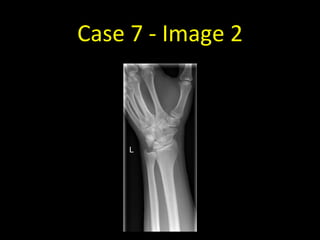

Case 7 - Image 2

Case 7

• Scaphoid fractures can be notoriously

difficult to see. Four views are obtained

when a scaphoid fracture is suspected.

• A comminuted fracture of the waist of

the left scaphoid is visible on this

scaphoid series - this example is easier

to spot than most scaphoid fractures

• If a scaphoid fracture is still suspected

despite not being visible on radiographs,

the wrist should be immobilised and

repeat radiographs performed in 7-10

days at which time the fracture may be

more apparent.